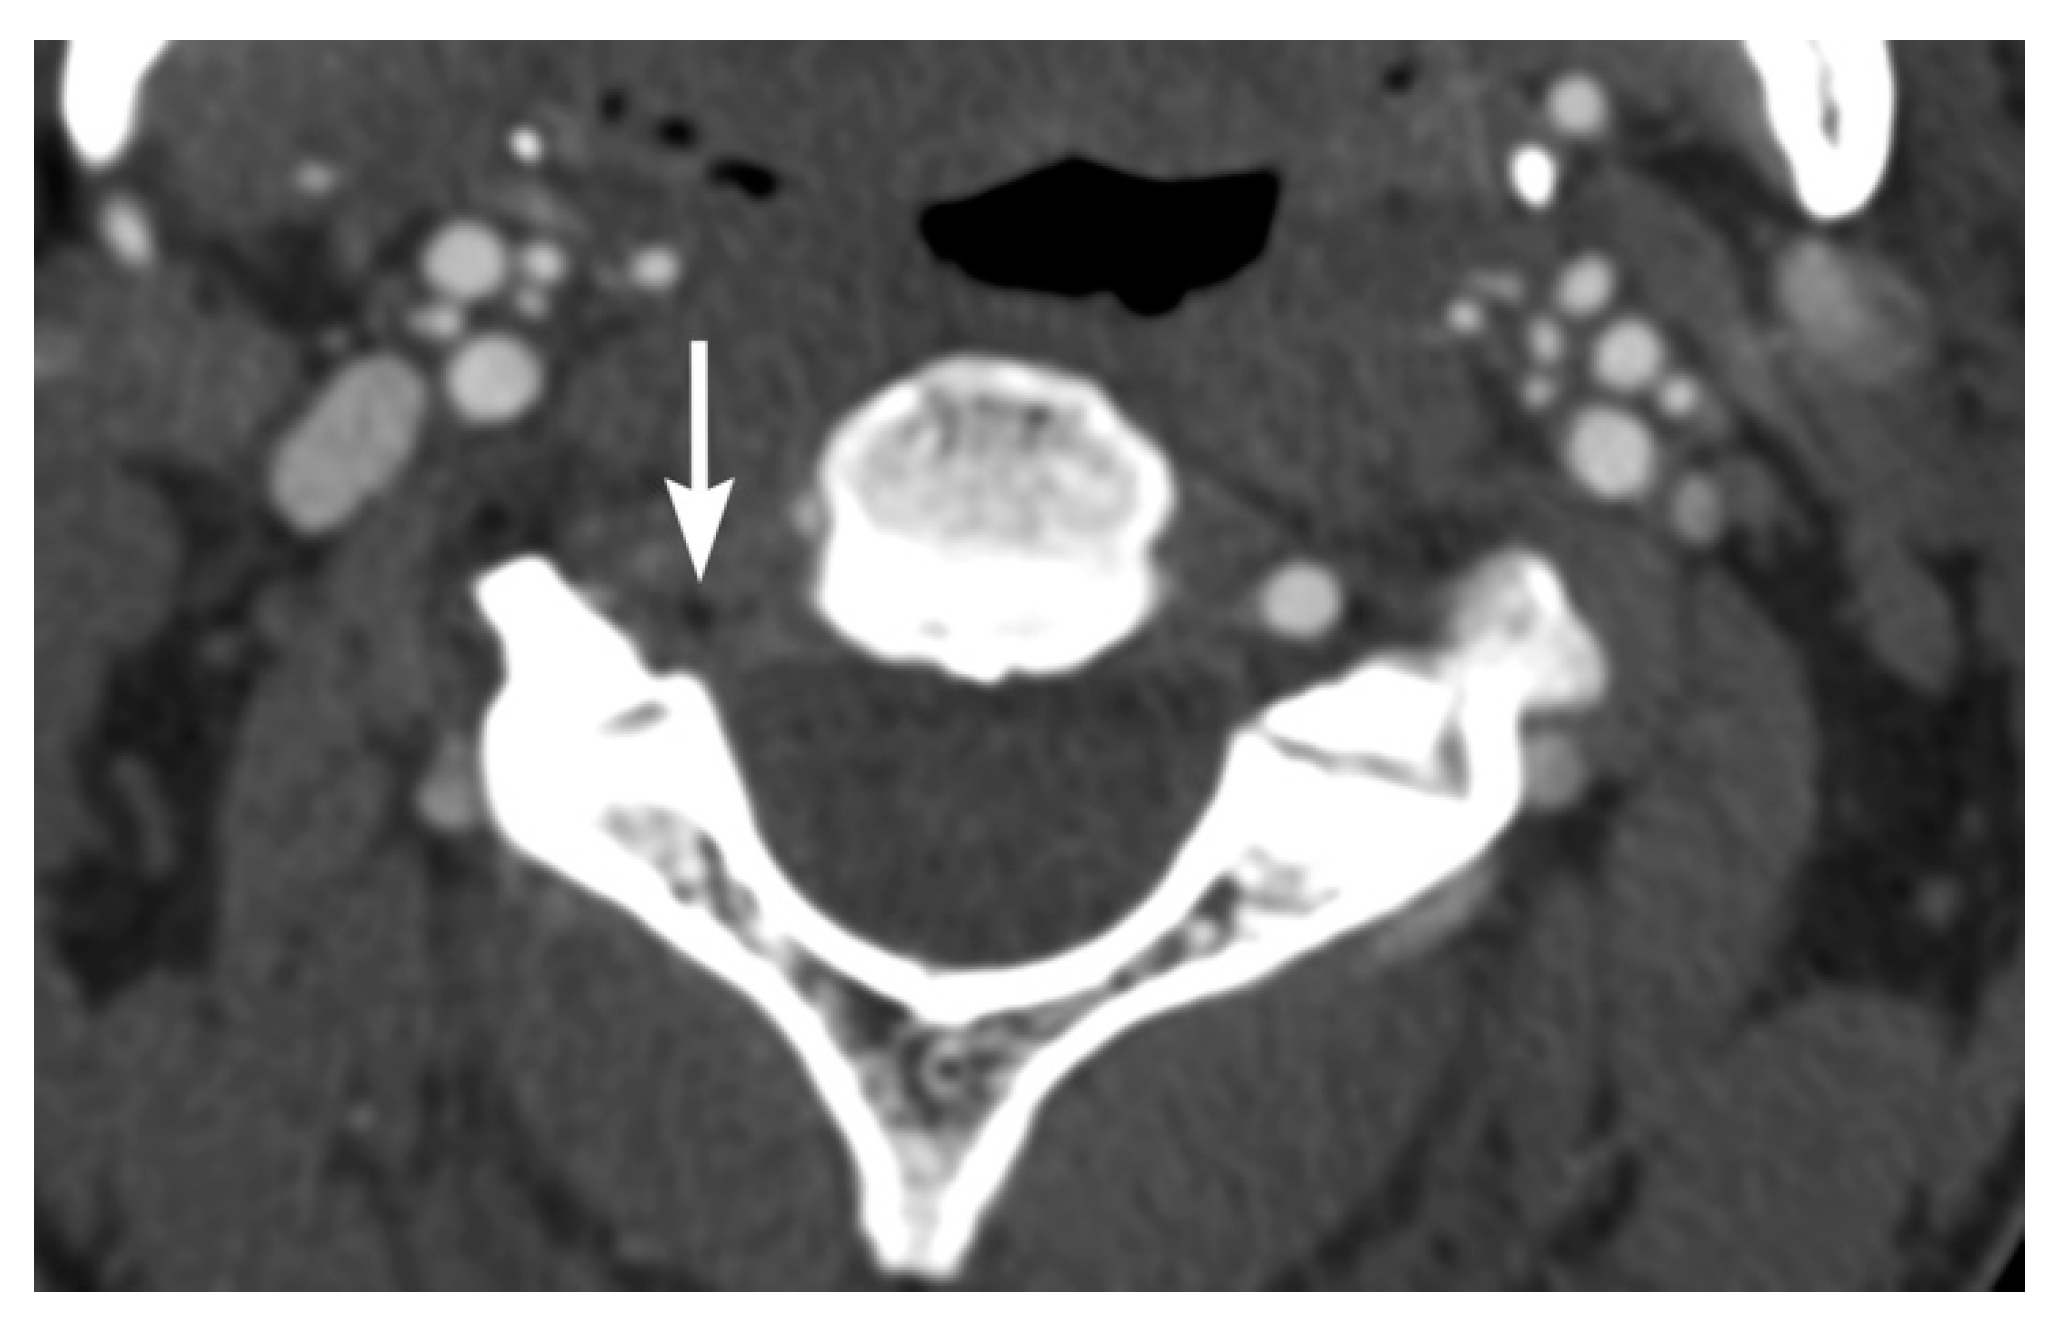

2. Imaging Techniques

3. Imaging Findings of Arterial Injury